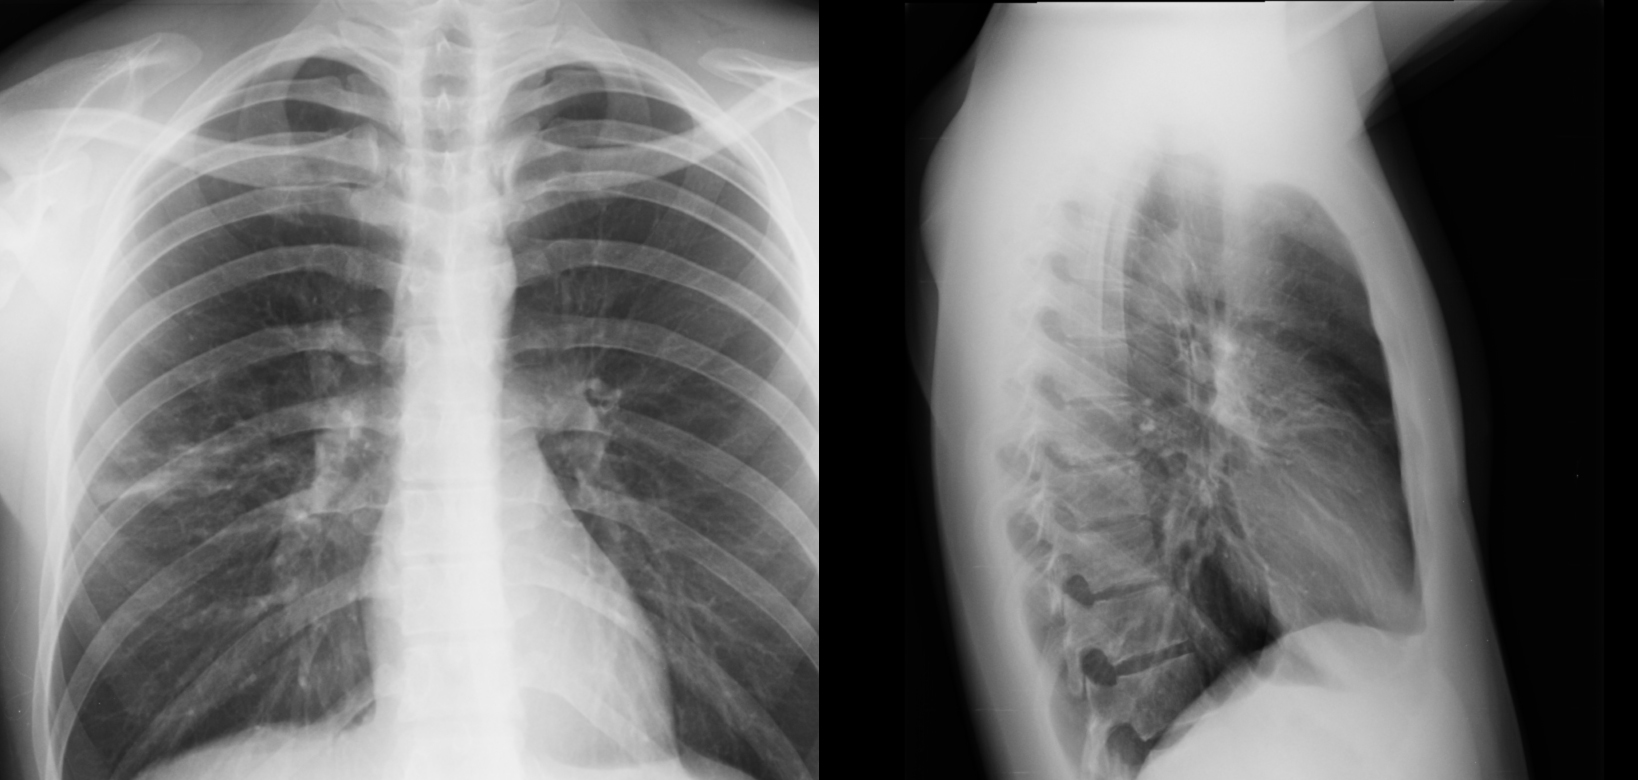

Снимок легких при туберкулезе является важным методом диагностики этого заболевания. На рентгеновских снимках можно увидеть изменения в легких, которые свойственны туберкулезу.

Очаговый туберкулез рентген

Рентген грудной клетки туберкулез

Фотографии снимков легких при туберкулезе

В данной статье представлены многочисленные фотографии снимков легких при туберкулезе, чтобы помочь вам понять, как выглядят изменения легких на рентгеновских снимках при этом заболевании.